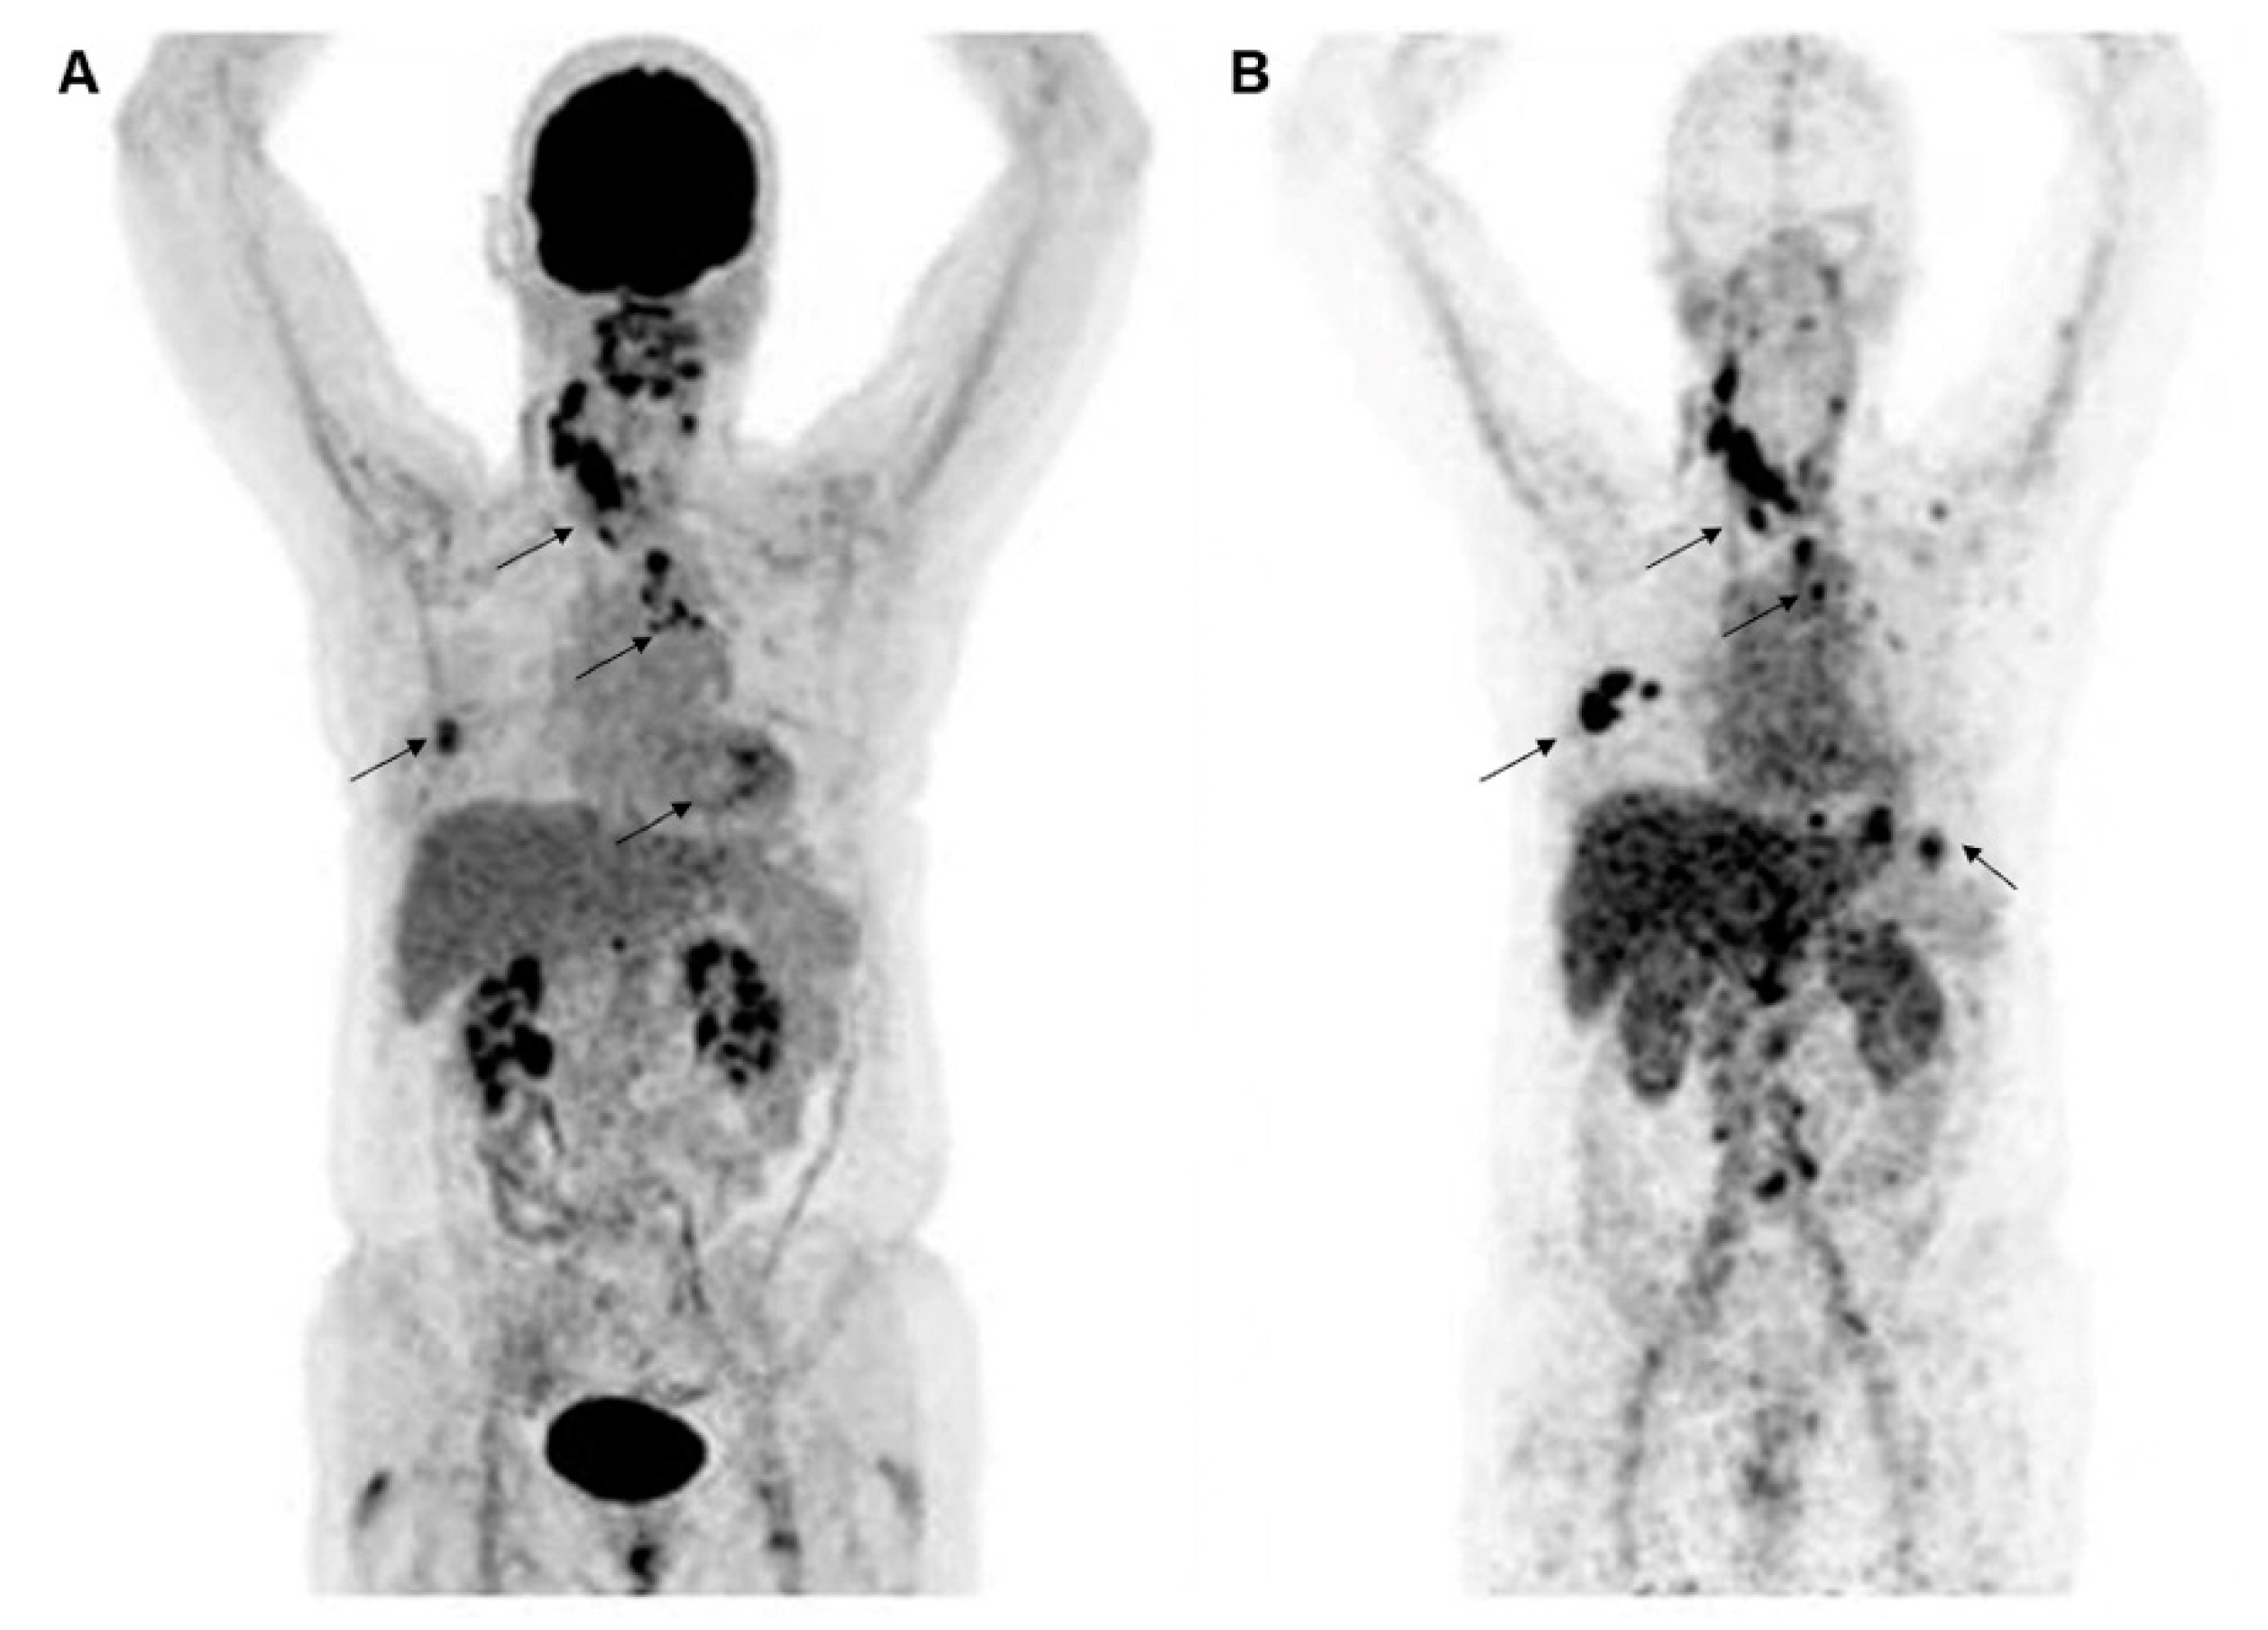

Figure 2.

Representative molecular PET images of a patient with HER2-positive BC were visualized by 18F-FDG (A) and HER2 (B) imaging with 89Zr-trastuzumab. Images are reproduced with permission from [30].